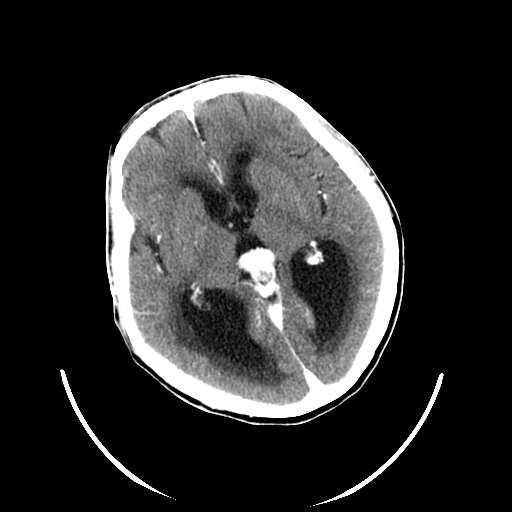

以下是引用zhangzhongshou在2007-10-8 19:16:00的发言:[br]大脑大静脉瘤[br]

以下是引用hhcckk在2007-10-9 10:03:00的发言:[br]galen';s静脉瘤又称大脑大静脉瘤,是由于动静脉短路,大量血流进入galen';s静脉(大脑大静脉),造成该静脉瘤样扩张所致,病理上典型的galen';s静脉瘤包括一明显扩张的囊状galen';s静脉和引流galen';s静脉的短路血管,,这些短路血管多来源于颈内动脉系统或基底动脉系统,多异常扩大、迂曲。巨大的galen';s静脉瘤可造成中脑压迫,导水管闭塞,引起梗阻性脑积水。[br]galen';s静脉瘤ct表现较典型,根据其部位、形态、增强前后表现及脑积水表现较易诊断。[br]支持张主任,此病人病灶强化明显,正常松果体增强后在病灶的后方可见,可以再做个mr,血管性的病灶在mr上有流空效应,增强后明显强化,诊断更有把握